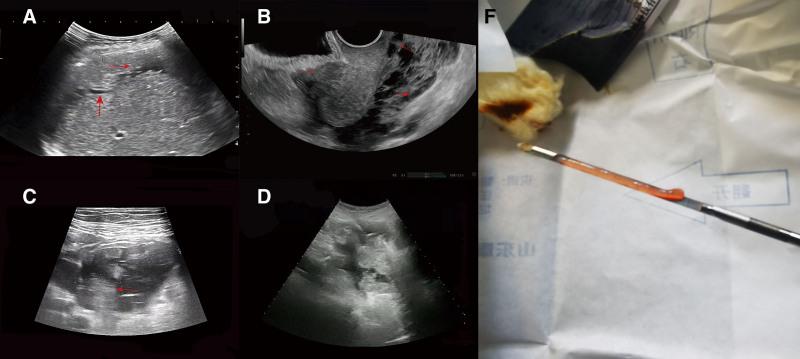

Initial imaging, including liver magnetic resonance imaging (MRI) and abdominal ultrasound, showed irregular liver margins and ascites, consistent with cirrhosis. However, subsequent diagnostic tests, including uterine MRI, positron emission tomography-computed tomography, and abdominal ultrasound, revealed features suggestive of PMP. Immunohistochemistry and histopathological examination of tissue samples confirmed low-grade mucinous adenocarcinoma of gastrointestinal origin, specifically from the appendix.

最初的影像学检查,包括肝脏磁共振成像(MRI)和腹部超声,显示肝脏边缘不规则及腹水,符合肝硬化表现。然而,随后的诊断检查,包括子宫MRI、正电子发射断层扫描-计算机断层扫描和腹部超声,发现了提示PMP的特征。组织样本的免疫组织化学和组织病理学检查证实为胃肠道来源的低级别黏液腺癌,具体来自阑尾。